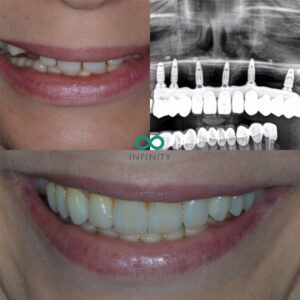

Using a 3D CBCT scan, I was able to get a detailed picture of her bone structure and dental health, which helped us explore all the possible options. I walked her through each choice, from dentures to implant-supported teeth, explaining the pros and cons of each. Ultimately, she chose to have dental implants with permanent teeth—a decision I wholeheartedly supported as the best solution for her.

She also had a clear vision of what she wanted for her smile. It wasn’t just about function; it was about aesthetics too. She wanted a natural-looking smile—one that could easily be mistaken for her own teeth. We worked together to design something beautiful, but realistic, with a natural charm that complemented her features perfectly.

Fast forward to today, and she’s now enjoying life with stunning, life-like teeth supported by Straumann dental implants. These implants are truly world-class—offering unparalleled stability, function, and aesthetics. Her new smile is radiant and natural, and it’s brought back her confidence in ways that words can’t fully capture.